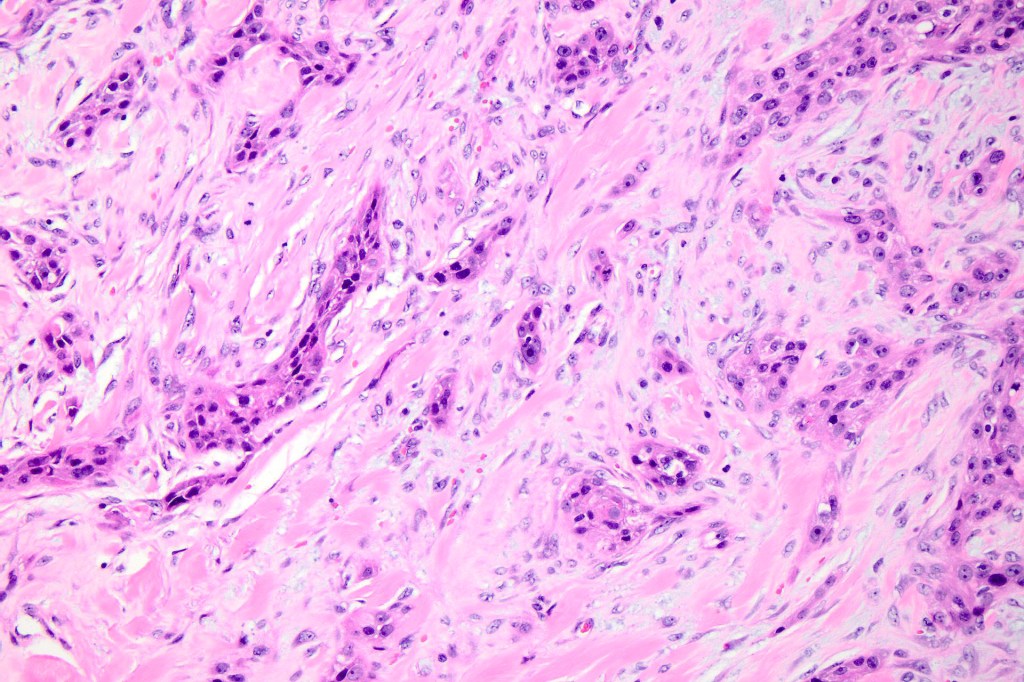

•Nuclear pleomorphism and nuclear hyperchromatism

•Marked mitotic activity

•Abnormal mitoses

•Stroma may be desmoplastic

•Spindle cell subtype